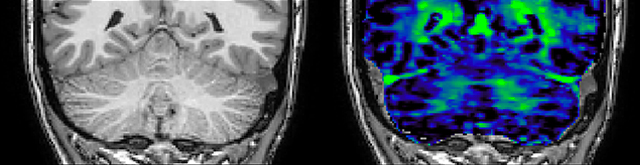

T1 - weighted

Myelin water imaging - T1 weighted

Myelin water imaging (echo 1)

Myelin water imaging with SENSE

Myelin water imaging with Compressed SENSE

With SENSE

With Compressed SENSE

Acquired resolution:

1 x 2 x 5 mm3

1.5 x 2 x 3 mm3

Number of echoes:

32 or 48

56

Echo spacing:

10 ms or 8 ms

7 ms

T1 - Weighted, Myelin Water Fraction Superimposed

MWI Spinal cord coverage

Spinal cord coverage

MWI Smaller, more isotropic voxels

Smaller, more isotropic voxels

MWI Excellent detail in quantitative maps

Excellent detail in quantitative maps

Images courtesy of Adam Dvorak, Department of Physics and Astronomy, University of British Columbia

20%

Myelin water fraction

0%